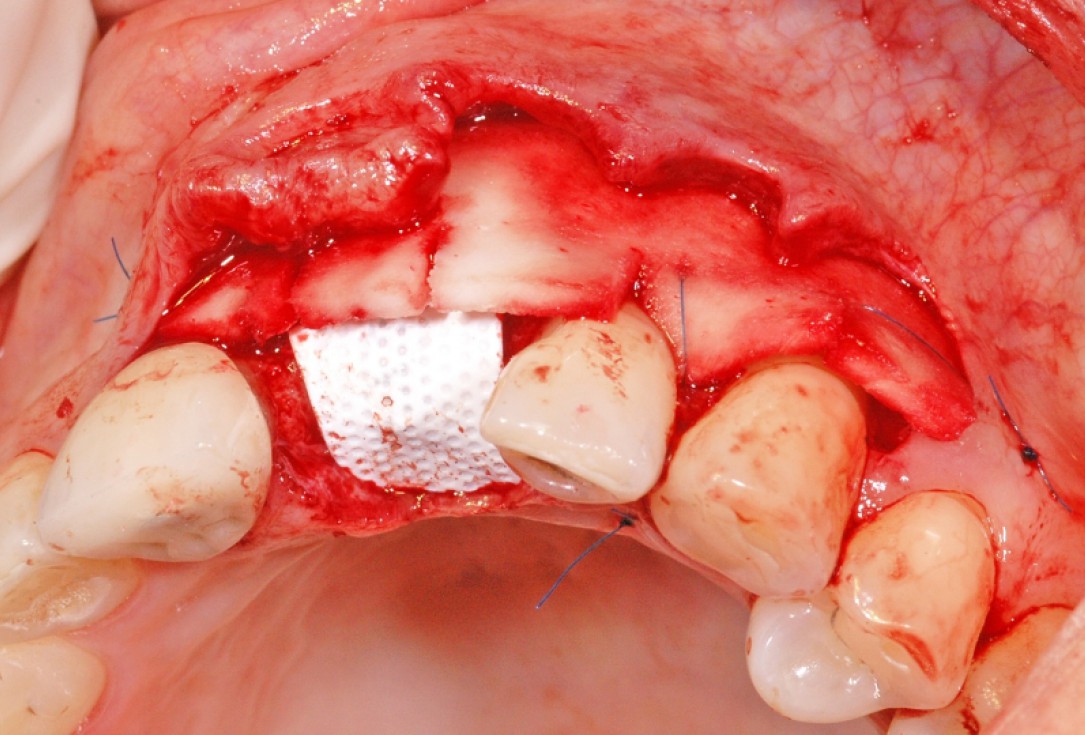

8/18 - Soft tissue thickening of the buccal side with mucoderm® and recession treatment of tooth 23GBR together with soft tissue augmentation with mucoderm® and maxresorb® - Dr. S. Scherg

9/18 - Additional placement of mucoderm®, crestally and linguallyGBR together with soft tissue augmentation with mucoderm® and maxresorb® - Dr. S. Scherg